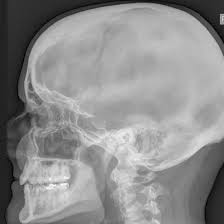

An X-Ray Left Mastoid Oblique is a specialized radiological scan of the mastoid bone behind the ear, performed in an oblique (angled) view. This scan helps in identifying mastoiditis (infection of the mastoid air cells), bone erosion, trauma, or congenital abnormalities. It is commonly prescribed when patients report persistent ear pain, swelling behind the ear, or hearing loss.

Medifyhome offers safe, efficient, and affordable diagnostic imaging with trusted NABL-certified labs. During the procedure, the patient’s head is tilted to capture the oblique view of the mastoid region, providing a detailed visualization of the bony air cells and inner ear structures. The results are instrumental in guiding ENT specialists or neurologists for treatment.

. An X-Ray Left Mastoid Oblique is a specialized angled X-ray that provides a detailed view of the left mastoid bone, located behind the ear.

It helps doctors detect infections, fractures, or other abnormalities affecting the mastoid region.